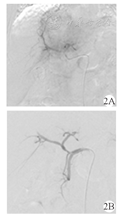

患者 男,57岁,乙型肝炎病史20余年。患者以"右上腹不适1周"为主诉入院。上腹部平扫CT(2015年10月21日)示:肝内Ⅳ段及Ⅷ段交界处可见8.2 cm × 6.2 cm团片状低密度区(图1A、图1B)。上腹部增强MRI(2015年10月22日)示肝左叶团块影,增强扫描病灶边缘不规则强化(图1C、图1D)。实验室检查:乙型肝炎表面抗原(HBsAg)阳性,甲胎蛋白(AFP)833.40 μg/L,癌抗原(CA)19-9 108.58 kU/L,肝功能Child-Pugh分级B级。临床诊断为原发性肝细胞癌,巴塞罗那肝癌分期(BCLC)B期。患者无介入治疗禁忌证,于2015年10月29日行肝动脉化疗栓塞术(TACE),术中造影见肝内肿瘤轻度染色(图2A),超选后肝右动脉予以碘化油5 ml +吡柔比星5 mg缓慢栓塞,辅助明胶海绵微粒(350~560 μm)50 mg+吡柔比星10 mg栓塞至肿瘤染色消失(图2B)。为明确病理诊断,术中经皮经肝超声定位下穿刺活检(16 G COOK活检针),术后病理(图3):肝细胞癌。术后第4天复查:AFP 263.50 μg/L,CA19-9 233.4 kU/L,肝功能基本正常。1个月后复查:AFP 712 μg/L,CA19-9 512.3 kU/L。于是,2015年12月7日再次行TACE,术中造影见肝肿瘤轻微染色(图4A),予以50 mg明胶海绵微粒(350~560 μm)10 mg+雷替曲塞2 mg+奥沙利铂50 mg栓塞肿瘤,造影见肿瘤染色消失(图4B)。第1次TACE术后1个月(2015年12月10日)复查上腹部CT示肝内见团片状、点状高低混杂密度影,较大切面为7.3 cm × 6.2 cm,局部突出于肝包膜之外,腹膜及肝被膜下见多发小结节状影,提示腹膜转移(图5A、图5B)。第1次TACE术后3个月(2016年2月14日)复查上腹部CT示肝内病灶较前缩小,腹膜多发结节状较前增多、增大(图5C);复查AFP上升至6 028 μg/L,腹水脱落细胞检查为腺癌。为控制腹膜转移瘤进展,患者口服索拉非尼(200 mg/次,2次/d)和腹腔灌注化疗(每3周腹腔灌注洛铂、雷替曲塞、香菇多糖及苦参碱)。第1次TACE术后6个月(2016年5月14日)复查上腹部CT提示肝内病灶缩小,坏死明显,但腹膜转移灶较前增多、增大,腹水较前增多(图5D);复查AFP >10 000 μg/L。患者于2016年6月20日不慎摔倒出现意识模糊伴发恶心呕吐,呕吐物为咖啡样物,随后出现心脏、呼吸骤停,临床死亡。

注:2A:术前造影见肝内团块状肿瘤染色,肝左右动脉供血;2B:肝动脉化疗栓塞术后造影见肿瘤染色消失